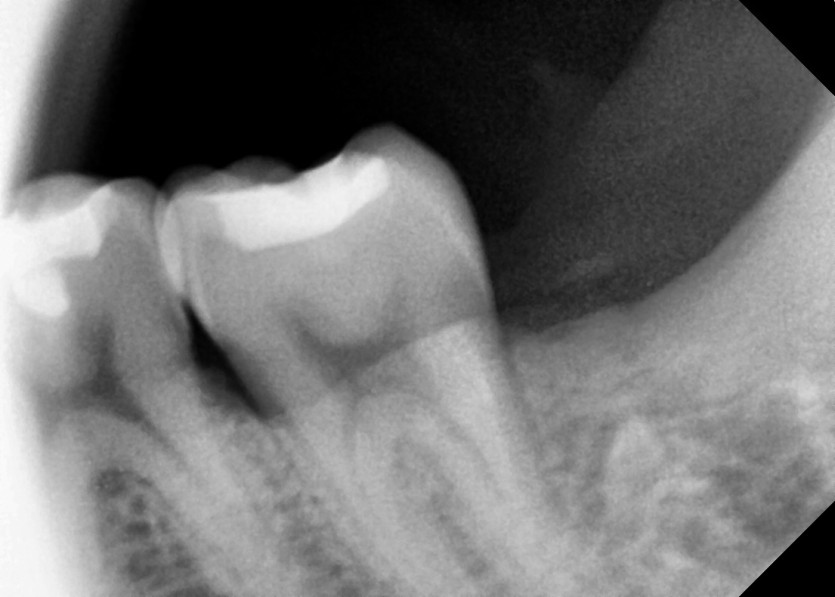

#38 사랑니 발치

구강 외과 전문의가 당일 발치했습니다.